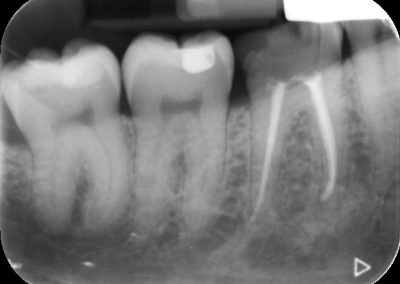

During the consultation, the dentist will first listen to your concerns and carry out appropriate tests to identify the right tooth that is causing pain. As a part of the diagnosis, your dentist will carry out various clinical tests to identify the right tooth and will take some radiographs which can aid in the diagnosis.

An access cavity is placed on the surface where the patient bites, to reach the root canals of the tooth. Once all the canals are identified, small files are used to remove the infected pulp.

Files of different sizes are used to eliminate bacteria and infection and to shape the canals. The canals are disinfected thoroughly with irrigants and later the canals will be sealed in 3 dimensions with a special medicament called gutta-percha to prevent reinfection of the tooth and the access cavity will be sealed with a temporary filling.